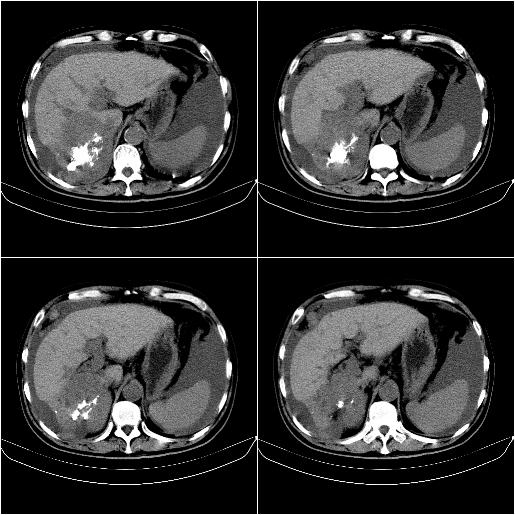

标题: CT21651:M,67Y,肝癌9月,介入术后3月。

m,67y,肝癌9月,介入术后3月。现腹胀、纳差、腹泻。

门静脉有很大的瘤栓,膈肌及膜膜有转移,不用再做了.

情况不好,门静脉癌栓、腹膜转移。

1)肝癌介入治疗术后碘油沉积不良。2)门静脉瘤栓形成,腹膜广泛性转移。3)肝硬化,脾大,腹水。4)慢性胆囊炎。